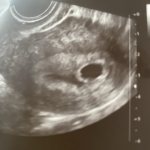

Девочки, вторая полоска день за днем ярче, но на УЗИ сказали неразвивающаяся беременность😭 нет смысла ждать? Прервать?

Сколько недель? Если 5-6 то ещё рано же определять сердцебиение

6 недель и дни еще какие-то есть